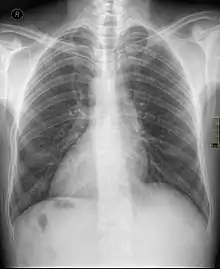

Dextrocardia

La dextrocardia es una situación en la que el corazón se encuentra en la mitad derecha del tórax debido a una causa de una alteración congénita .[1] Normalmente, el corazón se sitúa en la parte media del tórax, con su vértice o ápex inclinado hacia la izquierda; sin embargo, en esta malformación, ese orden es alterado y el corazón se ubica inclinado hacia el lado derecho del tórax.A menudo se asocia con otras anomalías del desarrollo y, en la mayoría de los casos, se diagnostica de forma incidental. Puede ocurrir por sí solo o puede ir acompañado de una inversión en la posición de otros órganos (denominado situs inversus totalis).[2]